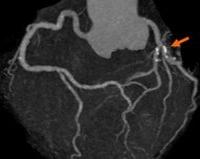

• Ишемическая ангиография. Классический инвазивный метод, который выполняется для визуализации внутренней поверхности коронарных сосудов. Обследование помогает выявить бляшки на стенках или в просвете кровеносных сосудов, но коронарная ангиография не может определить их плотность и химический состав.